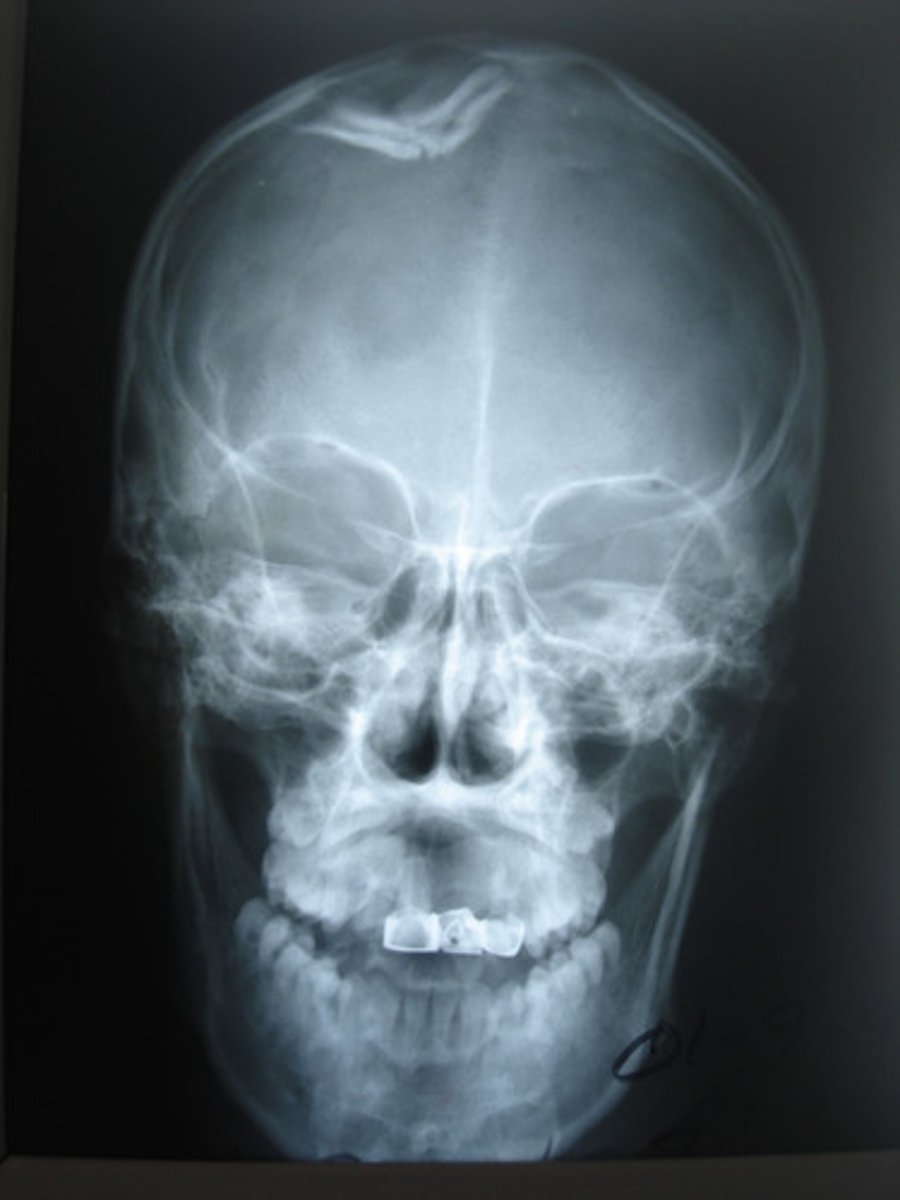

A fracture of the skull, a fragment is depressed

Depressed fx (ping-pong fx)

Fracture with fracture lines radiating from center point of injury in a starlike pattern

Stellate fx